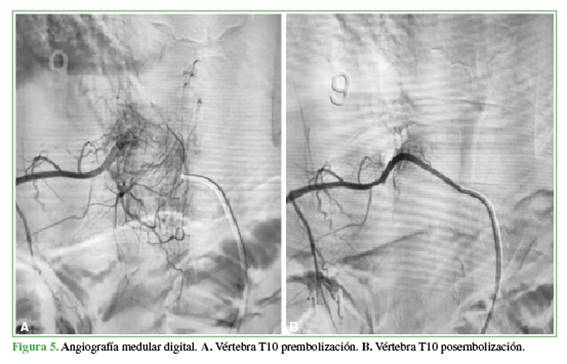

Sobre la base del diagnóstico y la clínica del paciente, se optó por adoptar una conducta quirúrgica. Se realizó una angiografía medular digital bajo anestesia general (Figura 5), la cual evidenció hipervascularización dependiente de T10 derecha. En el mismo acto, se efectuó un tratamiento endovascular de embolización con emboesferas.

Por último, frente a grandes tumores hipervasculares con alto riesgo de hemorragia, se debe considerar la embolización selectiva preoperatoria. Nuestro paciente fue sometido a este procedimiento como parte del tratamiento preoperatorio. En los últimos años, la embolización se ha preferido como primera opción cuando el diagnóstico es seguro, técnicamente factible y existe la posibilidad de intervención quirúrgica dentro de las 24-48 h posteriores. Se han informado tasas de curación cercanas al 87% con esta estrategia.23,24

En este caso, se realizó un curetaje agresivo con vaciado de la lesión, asociado a fenolización del lecho como método local. Se asoció con la descompresión amplia del arco posterior, por lo cual fue imperiosa la necesidad de fusión instrumentada. La embolización digital preoperatoria fue sumamente útil, no solo contribuyó al tratamiento posterior, sino que sirvió también para prevenir un sangrado masivo intraoperatorio, ya que el paciente presentaba un árbol vascular peridural extenso totalmente trombosado, que se podía observar en la resonancia preoperatoria.